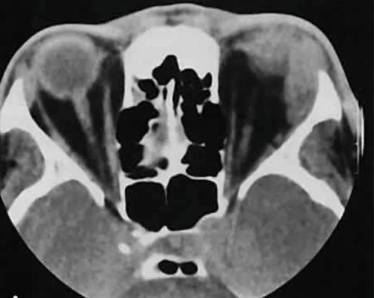

Спондилолистез со смещением одного или нескольких позвонков

Спондилолистез — это нетравматическое смещение позвонков. Обычно причиной является генетическая предрасположенность, из-за которой один или несколько позвонков смещаются из-за недостатка костных структур, удерживающих их на месте.

Кто и как диагностирует?

Диагностику проводит хирург с помощью рентгенографии и компьютерной томографии (КТ).